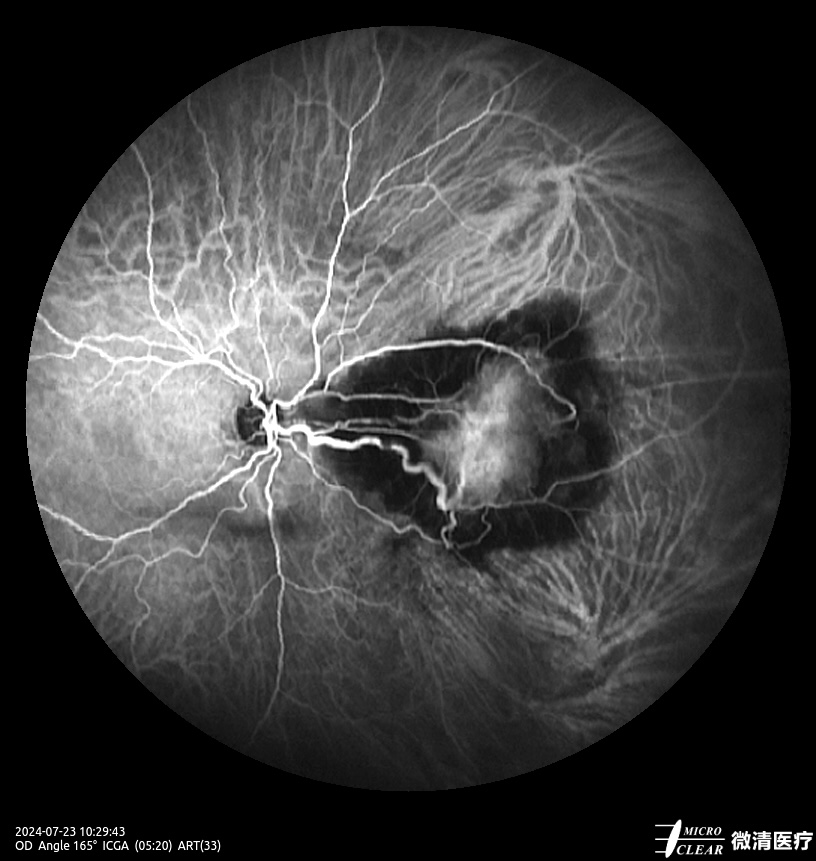

- 135° WA (Groothoekangiografie) – in één opname

Confocale Scanning Laser Oftalmoscoop (CSLO)

- Combinatie van drie confocale laserbronnen voor maximaal contrast en getrouwheid.

- Verbeterd confocaal ontwerp zorgt voor een betere scheiding van de netvlieslagen en verbeterde penetratie door cataract en oculaire troebelingen.